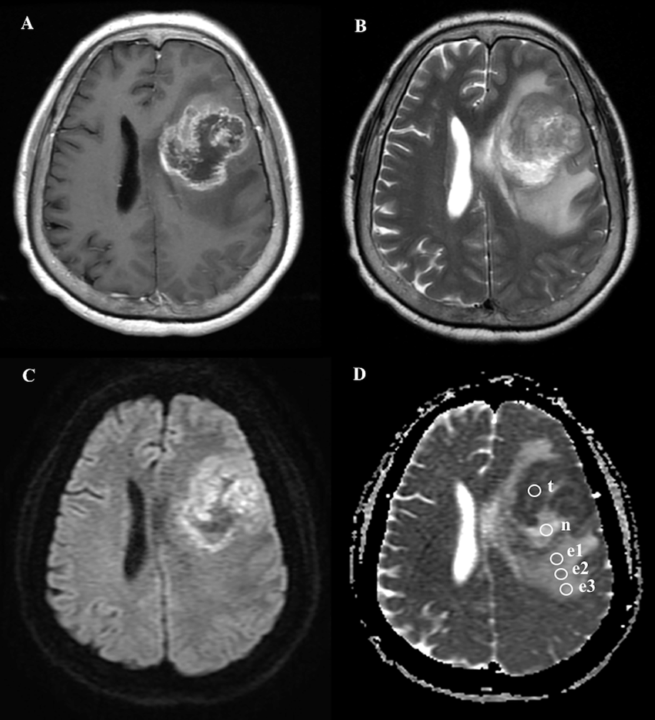

Glioblastoma Multiforme: Superando el Cáncer Cerebral Más Agresivo

El Glioblastoma Multiforme (GBM) es el tipo de Tumor Cerebral primario más común y agresivo